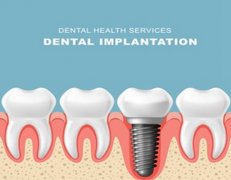

深圳烤瓷牙的材料,目前有金属材质和瓷材质。金属材质的烤瓷牙材料包括镍铬合金、金合金等。这些合金的生物相容性比较好,延展性也不相同,例如比较广泛应用的金合金材质延展以及边缘封闭性就比较好,可以做的比较薄,适合长期使用。瓷材质的烤瓷牙能够达到美观的作用,能够模拟天然牙的光泽和亮度。如果牙友们是在美观上进行改良,可以选择瓷材制。如果是对于磨牙的牙友们建议选择金属材质。